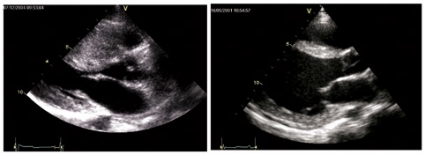

I begreppet »idrottshjärta« läggs i viss mån olika betydelser i dagligt tal och i vetenskaplig litteratur. Vi vill reservera begreppet för den normala anpassning till en hög fysisk aktivitet som ses hos individer som ägnar sig åt intensiv och långvarig träning. Under dynamiskt arbete med stora muskelgrupper, såsom löpning, skidåkning och cykling, finns ett behov av en stor ökning av hjärtminutvolymen för att tillfredsställa syretransportkraven, och hjärtat anpassar sig till detta ökade volymarbete med en ökning av kamrarnas inre dimensioner. Detta är väl kartlagt med ultraljudsmetodik vad avser vänsterkammaren [23]. På senare år har även studier av högerkammaren visat en motsvarande storleksökning [24]. Hjärtkamrarnas pumpfunktion, uttryckt tex som graden av förkortning av kamrarnas längd- och tvärdiametrar eller ejektionsfraktionen, förändras inte signifikant.

Graden av hjärtstorleksökning. Metaanalyser har visat att otränade unga personers vänsterkammarväggtjocklek uppgår till ca 9 mm medan den hos elitidrottare i uthållighetsgrenar i genomsnitt är 10 mm [25]. En kraftigt ökad väggtjocklek är alltså inget som kan skyllas på normal adaptation till idrott, och som yttersta gräns för normalitet hos uthållighetsidrottande använder man ofta 13 mm, vilket även det hör till de absoluta ovanligheterna hos hjärtfriska idrottare [26]. För vänsterkammardimensioner gäller att en slutdiastolisk vänsterkammardiameter överskridande 62–63 mm aldrig bör tillskrivas normal idrottsadaptation enbart [27].

Bedömningsproblem och differentialdiagnostik. Det är uppenbart att det kan uppkomma gränsdragningsproblem genom att en dilatation av hjärtrummen dels kan ses som naturlig adaptation till idrott, dels kan förekomma i tidiga skeden av tex dilaterad kardiomyopati eller myokardit.

Likaså ger hypertrof kardiomyopati en väggtjockleksökning som i gränsfall är problematisk att skilja från en mer normal hypertrofi hos personer inom övre delen av normalspektrum. Hjärtats diastoliska funktion, dvs fyllnadsfunktionen, påverkas tidigt vid patologiska former av hypertrofi, t ex vid hypertoni eller kardiomyopati. Den diastoliska hjärtfunktionen är normal hos friska idrottande personer även med en väggtjocklek inom övre referensintervallet [30, 31]. Även strukturellt och på gensignaleringsnivå har klara skillnader mellan patologisk och fysiologisk hypertrofi identifierats [32].

För en korrekt bedömning av om ekokardiografiska fynd är normala eller ej för en idrottsutövare fordras kunskap om gränserna för normalitet i förhållande till den idrott som utövas. En träningsanamnes är nödvändig, och ibland kan ett arbetsprov ge vägledning. Det fordras mer träning än motionsidrottande ett par gånger i veckan för att utveckla en signifikant hjärtstorleksökning! Både över- och underdiagnostik kan förekomma om elitidrottsmän genomgår ekokardiografi med sedvanliga bedömningsgrunder och utan kännedom om den grundläggande idrottsfysiologin. Såväl en friskförklaring på felaktiga grunder som en ogrundad sjuklighetsklassificering kan ha mycket stor betydelse för den individuelle idrottaren. Dessa bedömningar kräver omsorg och ofta specialistbedömning. Kompletterande information, som fysikaliskt status, kroppsbyggnad, kön, hereditet (eventuellt undersökning av föräldrar eller syskon), kan behöva vägas in för att kunna skilja idrottshjärta från patologisk hjärtförstoring. I speciella fall kan en period av träningsuppehåll tillgripas; då går »idrottshjärtat« i regress, men däremot inte eventuell kardiomyopati.